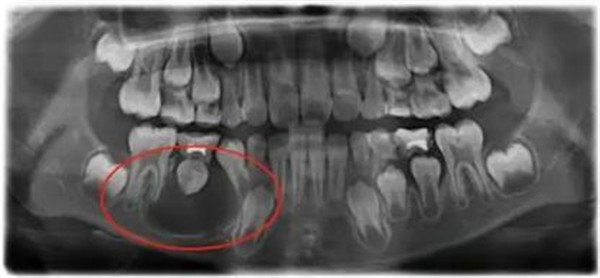

3.损伤恒牙胚(最严重的后果之一)

乳牙牙根下方埋藏着恒牙的“种子”——恒牙胚,乳牙根尖周的炎症会直接通过组织间隙“攻击”恒牙胚,造成多维度损伤:

·恒牙发育不全

·恒牙形态异常

·阻碍恒牙萌出